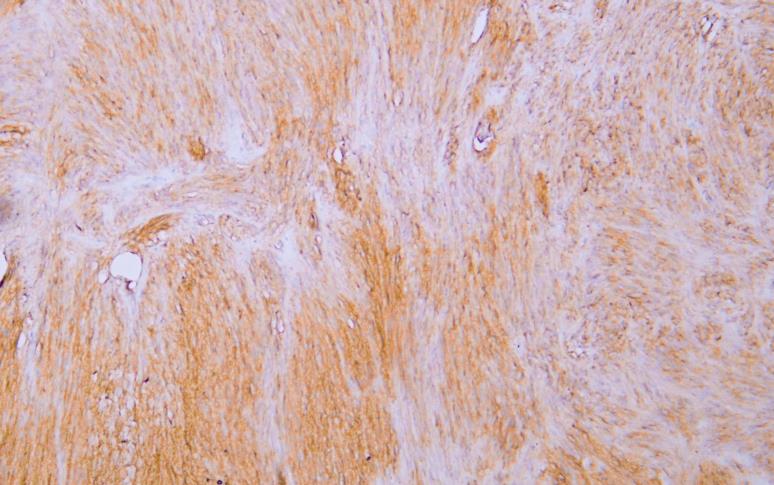

CD117 is a cell membrane protein encoded by the c-kit proto-oncogene and is a type III transmembrane protein tyrosine kinase growth factor receptor. CD117 is expressed in mast cells, melanocytes and interstitial cells of Cajal. CD117 is positive in 80-100% of gastric stromal sarcoma (GIST) . CD117, as a specific marker for immunohistochemical examination of gastric stromal sarcoma (GIST) , can be used to clinically guide the personalized target drug (Gleevec) treatment of GIST patients. CD117 can also be used to identify mast cell tumors in lymphoma and as a marker for some testicular germ cell tumors.

IHC; WB; IF; ELISA

IHC, 1:200-1:1000 | WB, 1:500-1:2000 | IF, 1:100-1:500 | ELISA, Recommended starting concentration is 1 µg/mL. Please optimize the concentration based on your specific assay requirements.